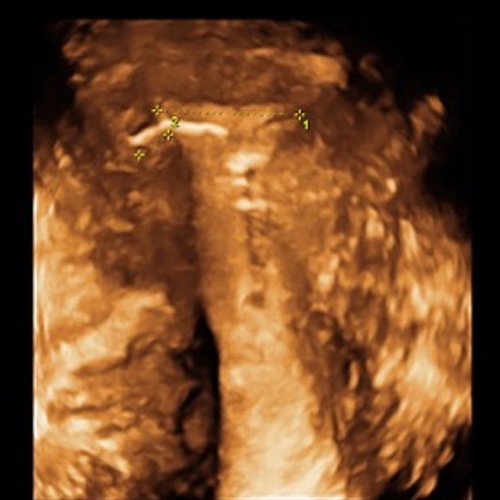

3D Bild eines perfekt sitzenden IUBTM-Kupferperlenballs.

Man sieht die relativ dünne Muskulatur am oberen Ende der Höhle (hier würde eine Kupferkette z.B. nicht verankert werden können). Auch fällt auf, dass die Höhle nur die 15mm Durchmesser "zur Verfügung" stellt. (Die kleinste herkömmliche Spirale braucht fast doppelt so viel Platz).

Gleiches Bild zum vereinfachten Verständnis. Kupferperlen liegen in der Mitte der Gebärmutterhöhle. Der Gebärmutterkanal ist aufgehellt. Die Gebärmuttermuskulatur ist in der Originalfarbe geblieben. Das umliegende Gewebe (im wesentlichen Darmschlingen) ist grau.